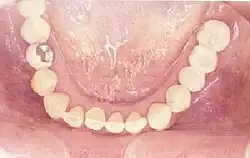

Zahnloser Kiefer

Manche Prothesenträger klagen über einen schlechten Sitz ihrer Prothese oder schmerzhafte Druckstellen. Haftmittel oder mechanische Hilfen lösen diese Probleme oft nicht zufriedenstellend. Implantate können in diesen Fällen das Mittel der Wahl sein. Der Tragekomfort einer Prothese kann so verbessert werden.

Die Befestigung von Totalprothesen an Implantaten wird häufiger im zahnlosen Unterkiefer, als im zahnlosen Oberkiefer durchgeführt, weil Unterkieferprothesen auch häufiger Probleme bereiten. Dies liegt an der geringen Saugwirkung und der kleineren Auflagefläche einer Unterkieferprothese. Im Unterkiefer können zwei Implantate genügen, wobei die Kraftverteilung auf vier Implantate von Vorteil ist. Im Oberkiefer sollten aufgrund der weicheren Knochenstruktur mindestens vier Implantate eingesetzt werden.[66]

Die Implantate können über Stegverbindung (eventuell mit Friktionshilfen) miteinander verbunden werden. Das dient sowohl der Stabilisierung der Implantate als auch der besseren Prothesenverankerung. Bei einer guten Primärstabilität ist in bestimmten Fällen eine Sofortbelastung möglich.

Sind etwa 6 bis 8 Implantate vorhanden, kann eine Totalprothese allein auf diesen abgestützt werden. Eine Belastung der Kieferkämme entfällt dann, so dass kein Knochenabbau zu befürchten ist. Bei dieser Anzahl von Implantaten ist alternativ eine festsitzende Zahnersatzversorgung möglich. Ursprünglich als Sozialindikation gedacht, sind inzwischen verschraubte Brücken auf jeweils vier Implantaten im Ober- oder Unterkiefer möglich.[67][68] Dadurch können Kosten und Behandlungsdauer reduziert werden. Die Verweildauer ist bei dieser Art der Versorgung vergleichbar mit dem konventionellen Vorgehen.[69]